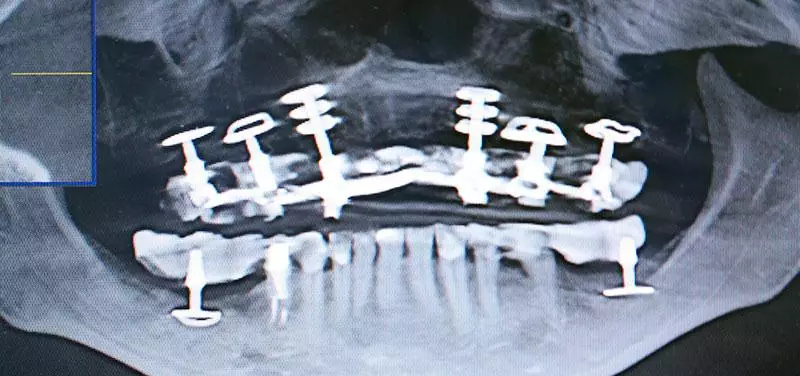

Базальная имплантация выполняется в несколько этапов. На первичном приеме стоматолог осматривает ротовую полость пациента, затем для выявления скрытых проблем назначает рентгенографию или КТ. Также исследование помогает оценить структуру и плотность костной ткани, рассчитать промежутки между имплантом и соседними зубами. Лучшим способом подготовки к установке имплантов является создание индивидуальной 3D-модели пациента, но делается это далеко не всегда.

Классические, или современные, представляют собой удлиненные штифты из титана конической формы. Их длина 20-35 мм, что объясняется глубиной установки. Их особенность в том, что сам имплант и абатмент на нем для крепления протеза объединены в единую конструкцию. К тому же для быстроты и простоты установки на них имеется выраженная резьба.

Скуловые импланты – это изделия из медицинского титана, длина которых достигает 60 мм. Применяются они во время протезирования на верхней челюсти, вживляются в глубокую скуловую кость под углом, что обеспечивает протезу необходимую стабильность во время эксплуатации.